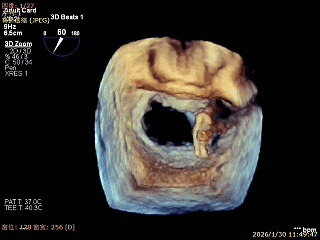

3D Enface 2区及3区前叶脱向左房

3D Enface 可见反流由2区3区从前后冲出